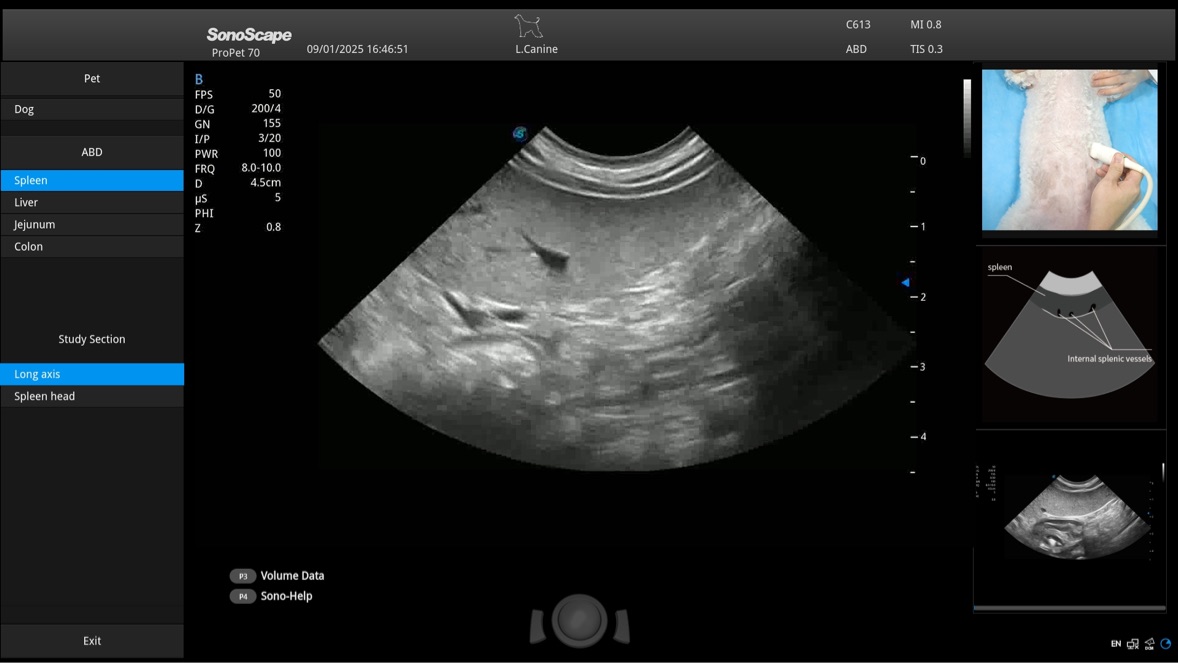

Przy pracach nad aparatem ProPet 60 uwzględniono najważniejsze preferencje i potrzeby weterynarzy, oferując finalnie przystępne cenowo i odpowiednio wyważone połączenie znakomitej precyzji klinicznej, zwiększonej wydajności i przemyślanego przebiegu pracy, niezastąpione w codziennej praktyce weterynaryjnej. Dzięki dostępowi do pełnej gamy głowic HD rozwiązanie to spełnia wszystkie potrzeby w zakresie obrazowania, umożliwiając wykonywanie badań jamy brzusznej, małych narządów, ortopedycznych, badań podczas rozrodu, a nawet badań serca i klatki piersiowej, a to wszystko przy doskonałym stosunku jakości do ceny.